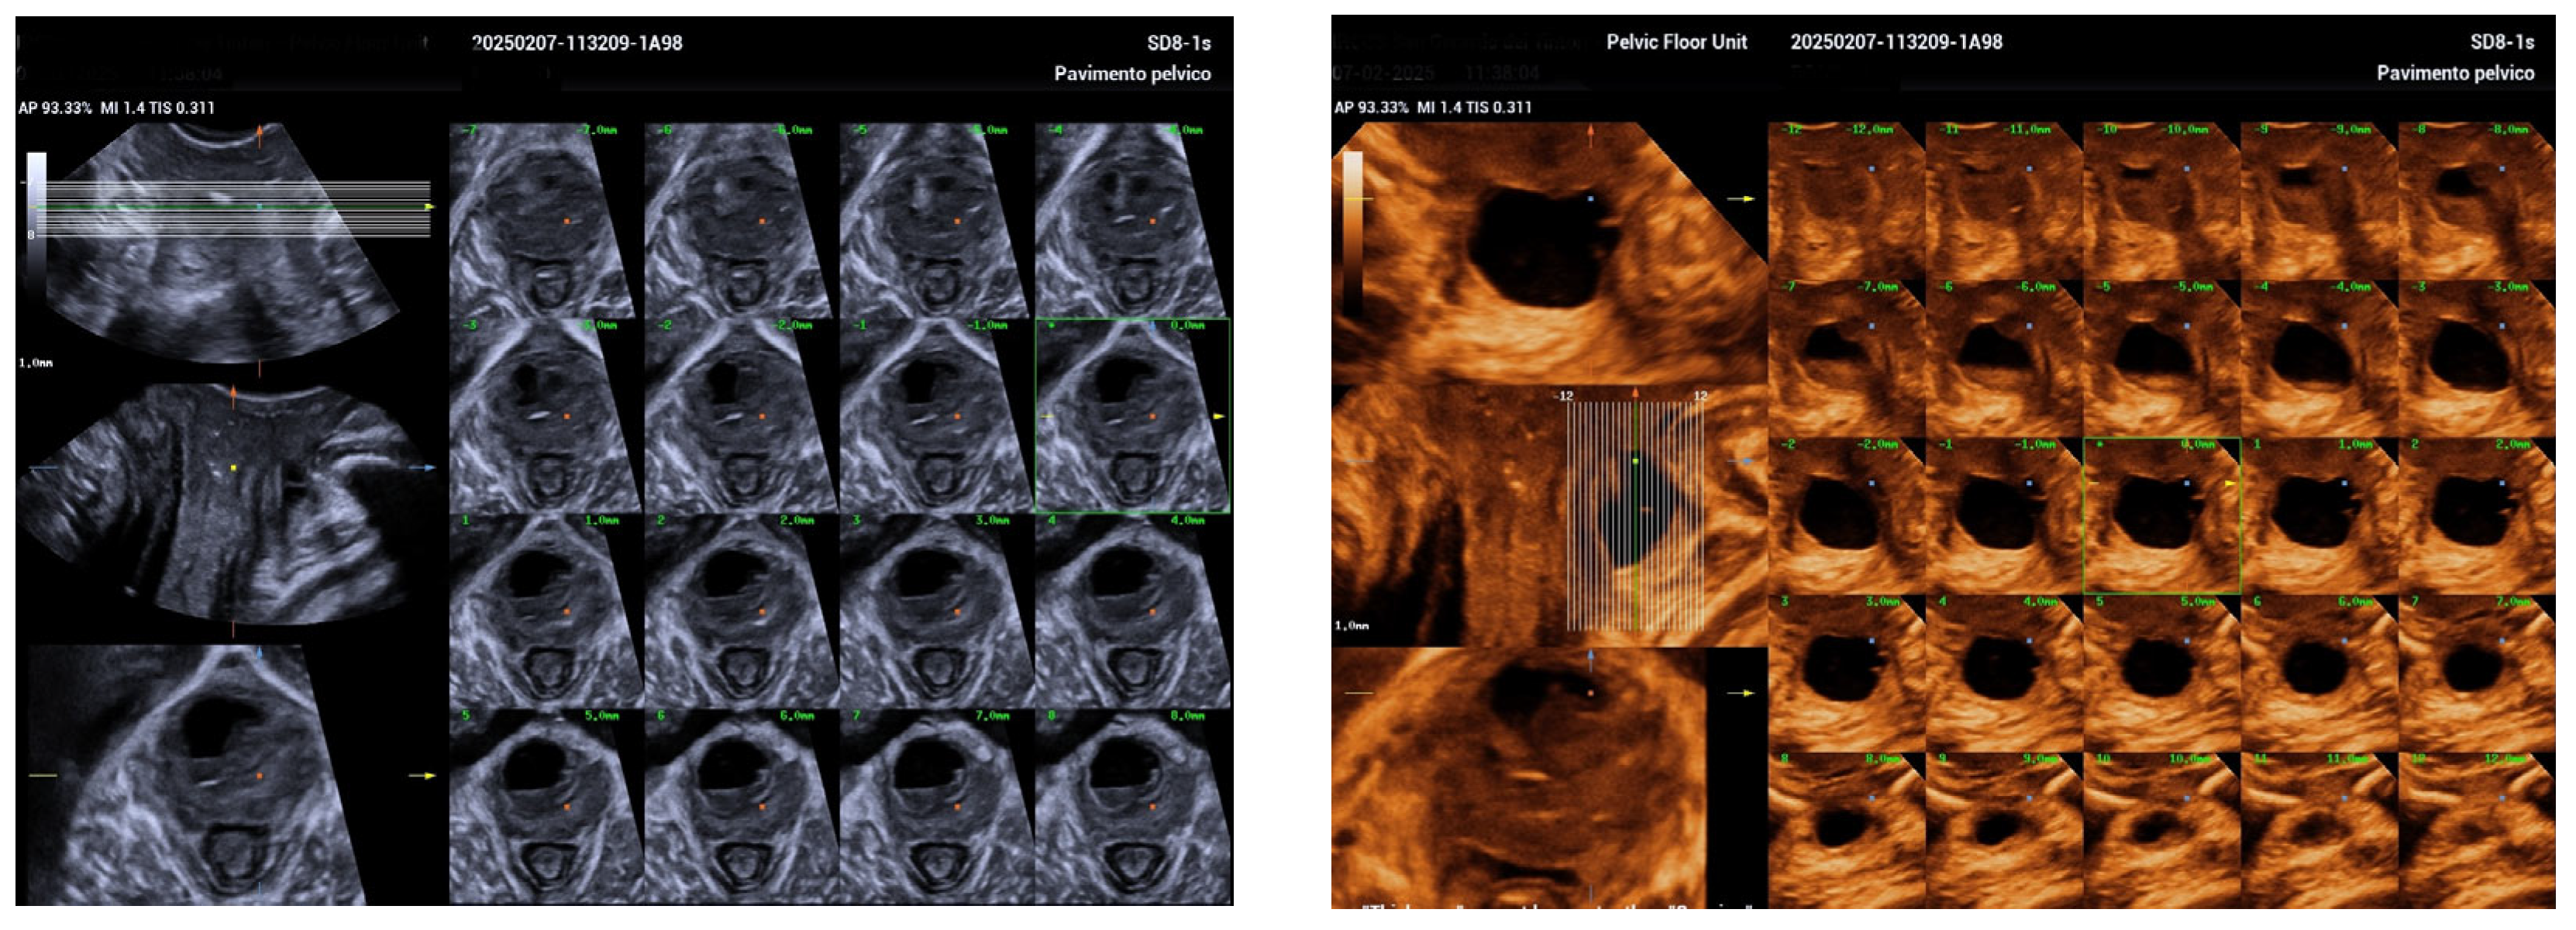

Managing Urethral Diverticulum During Pregnancy Utilizing Advanced Ultrasonographic Techniques: A Literature Review and Case Study

2. Case Report

| Jeong et al. [5] | Suprapubic pain, purulent discharge, leakage | 5.5 cm | TVUS, TPUS, 3D ultrasound at 34 weeks | Antibiotics; aspiration considered | Planned vaginal delivery | Postpartum diverticulectomy |